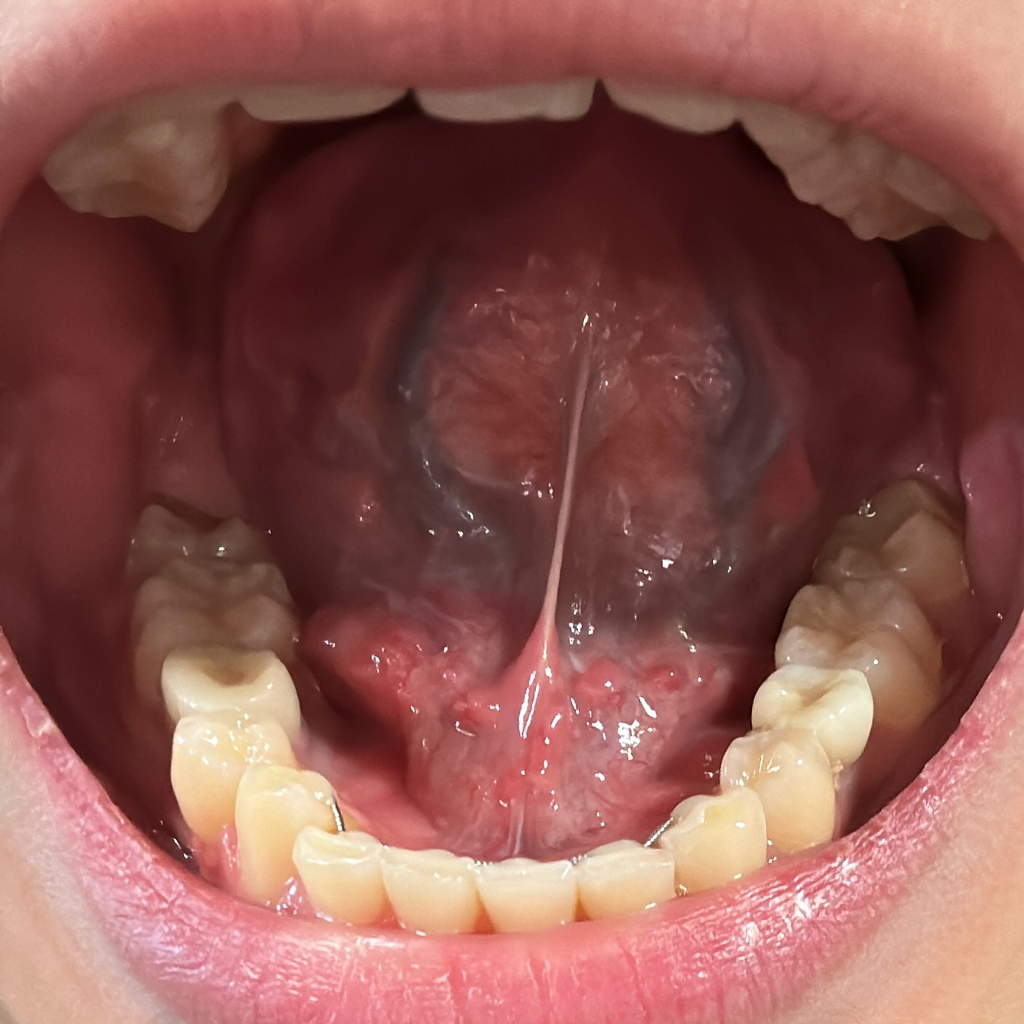

안녕하세요. 서민석 의사입니다.

구내염인것 같습니다. 통증이 있다면 소염진통제를 드시고 구강연고를 사서 발라보셔도 되겠습니다.